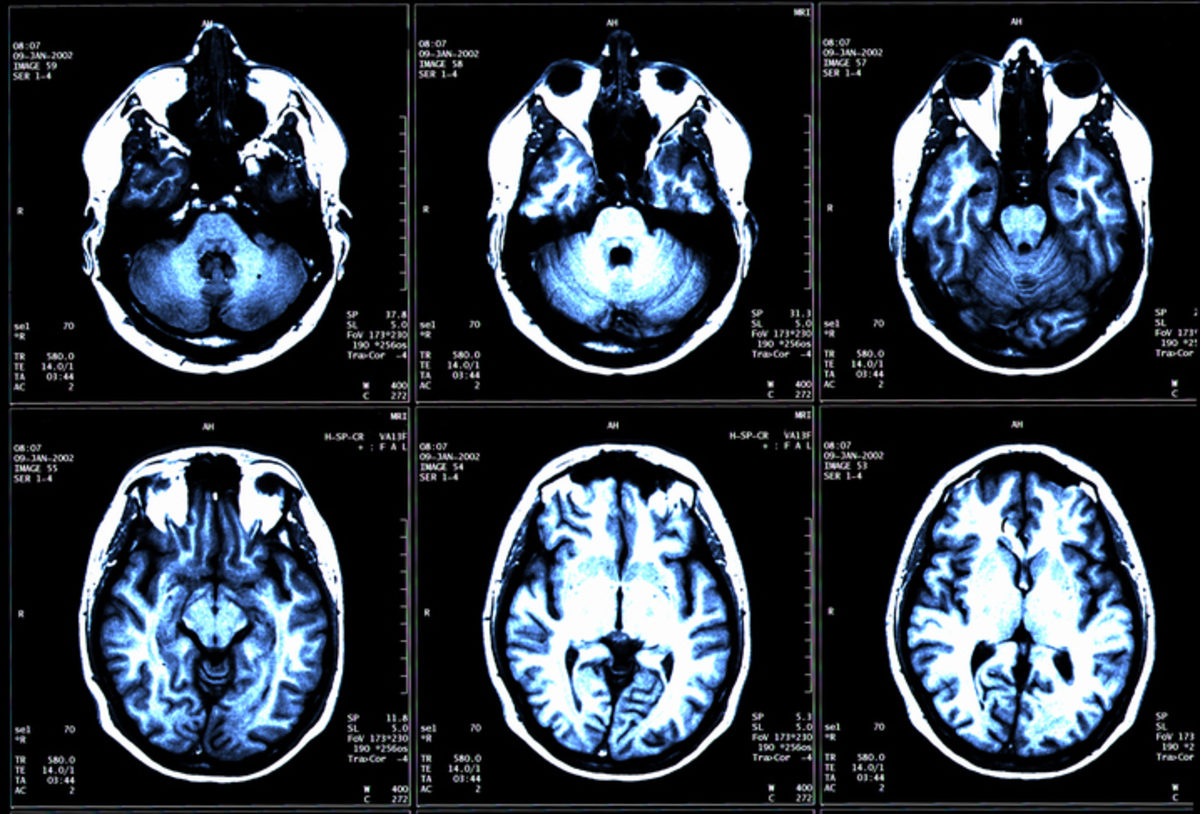

Six panels of an MRI scan.